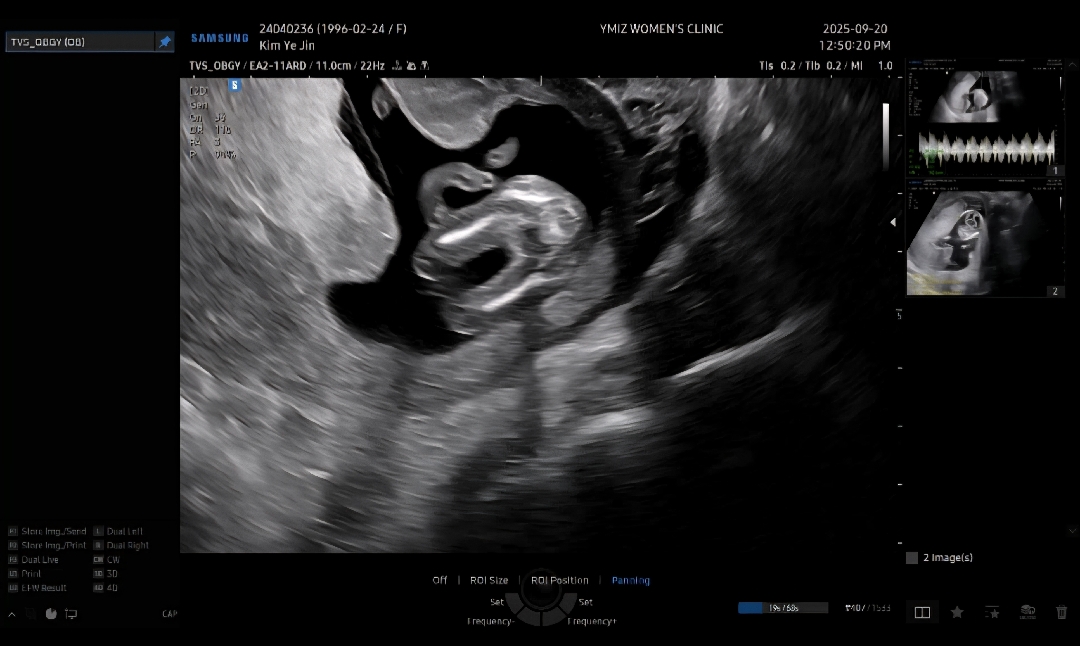

14주0일차 초음파 성별

14주0일차 초음파 보고왔어요 배초음파로 볼때는 태반사이에 끼여있어서 잘안보인다고 질초음파보자고 하셨고 다리 사이 매끈해서 이변은 없이 딸일거라고 하셨는데 성별 반전 있을까요?